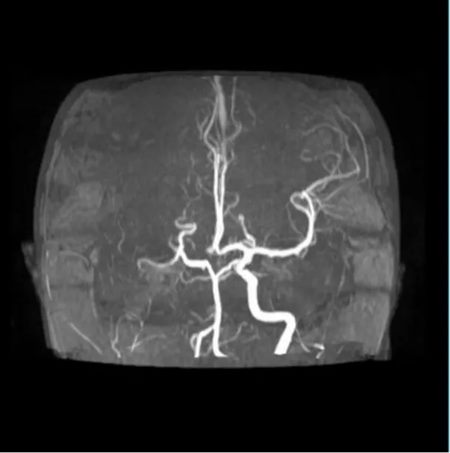

清晨,急诊科送来一名12岁的女孩。突发偏瘫、不能说话——确诊为“急性脑梗死”。

神经内科评估、神经外科接力、影像瞬间出片……

最终决定:脑血管造影 + 经皮颅内动脉取栓术。

手术台上,团队从她堵塞的颈内动脉中,取出一条近10厘米长的血栓。

血流恢复的那一刻,手术室里所有人都松了一口气。